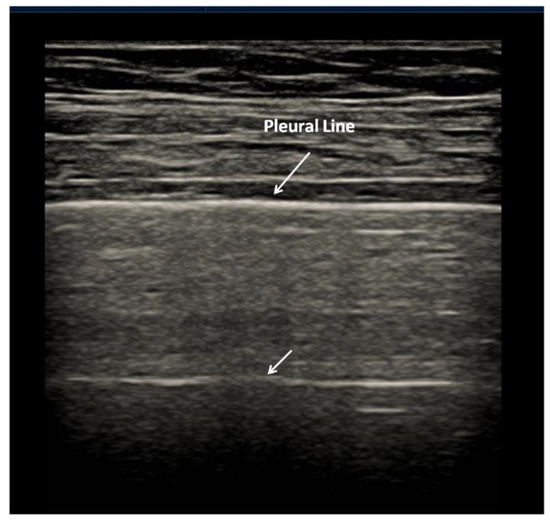

2.1. Characteristics of the Pleural Line

| 0 | Pleural line is regular. Horizontal artifacts and mirror effects are present. Normal lung. |